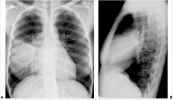

Bệnh lao kê là một dạng bệnh lao đặc trưng bởi các tổn thương nhỏ với kích thước 1–5 mm lan khắp cơ thể. Bệnh lao kê có thể lây nhiễm bất kỳ cơ quan nào như phổi, gan và lá lách. Vậy nguyên nhân và triệu chứng của bệnh là gì? Làm cách nào để chữa trị bệnh hiệu quả? Tham khảo ngay bài viết dưới đây để hiểu rõ hơn nhé!